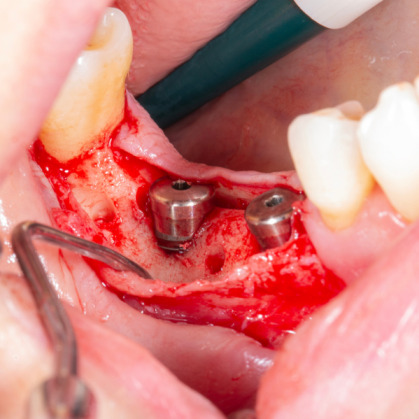

Ana sayfa > Klinik Vakalar > Diş çekiminin yıllar önce yapılmış olmasına bağlı olarak ince kemik varlığında implant ve kemik grefti uygulandı

Diş çekiminin yıllar önce yapılmış olmasına bağlı olarak ince kemik varlığında implant ve kemik grefti uygulandı